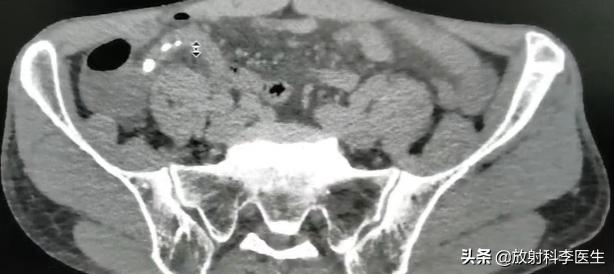

急性阑尾炎的CT表现:阑尾增粗,直径>6mm,阑尾壁增厚,阑尾腔内见粪石形成,阑尾周围脂肪间隙模糊,邻近肠管管壁可增厚,侧腹膜可增厚,有时可引起局限性腹膜炎表现,阑尾穿孔后可形成阑尾周围脓肿,有时可见气液平面。

急性阑尾炎伴粪石形成